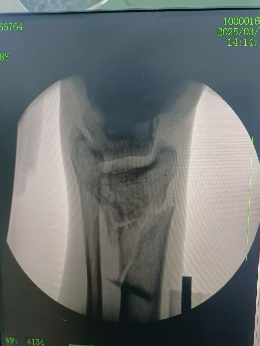

牽拉并透視

調整機械臂,輔助復位